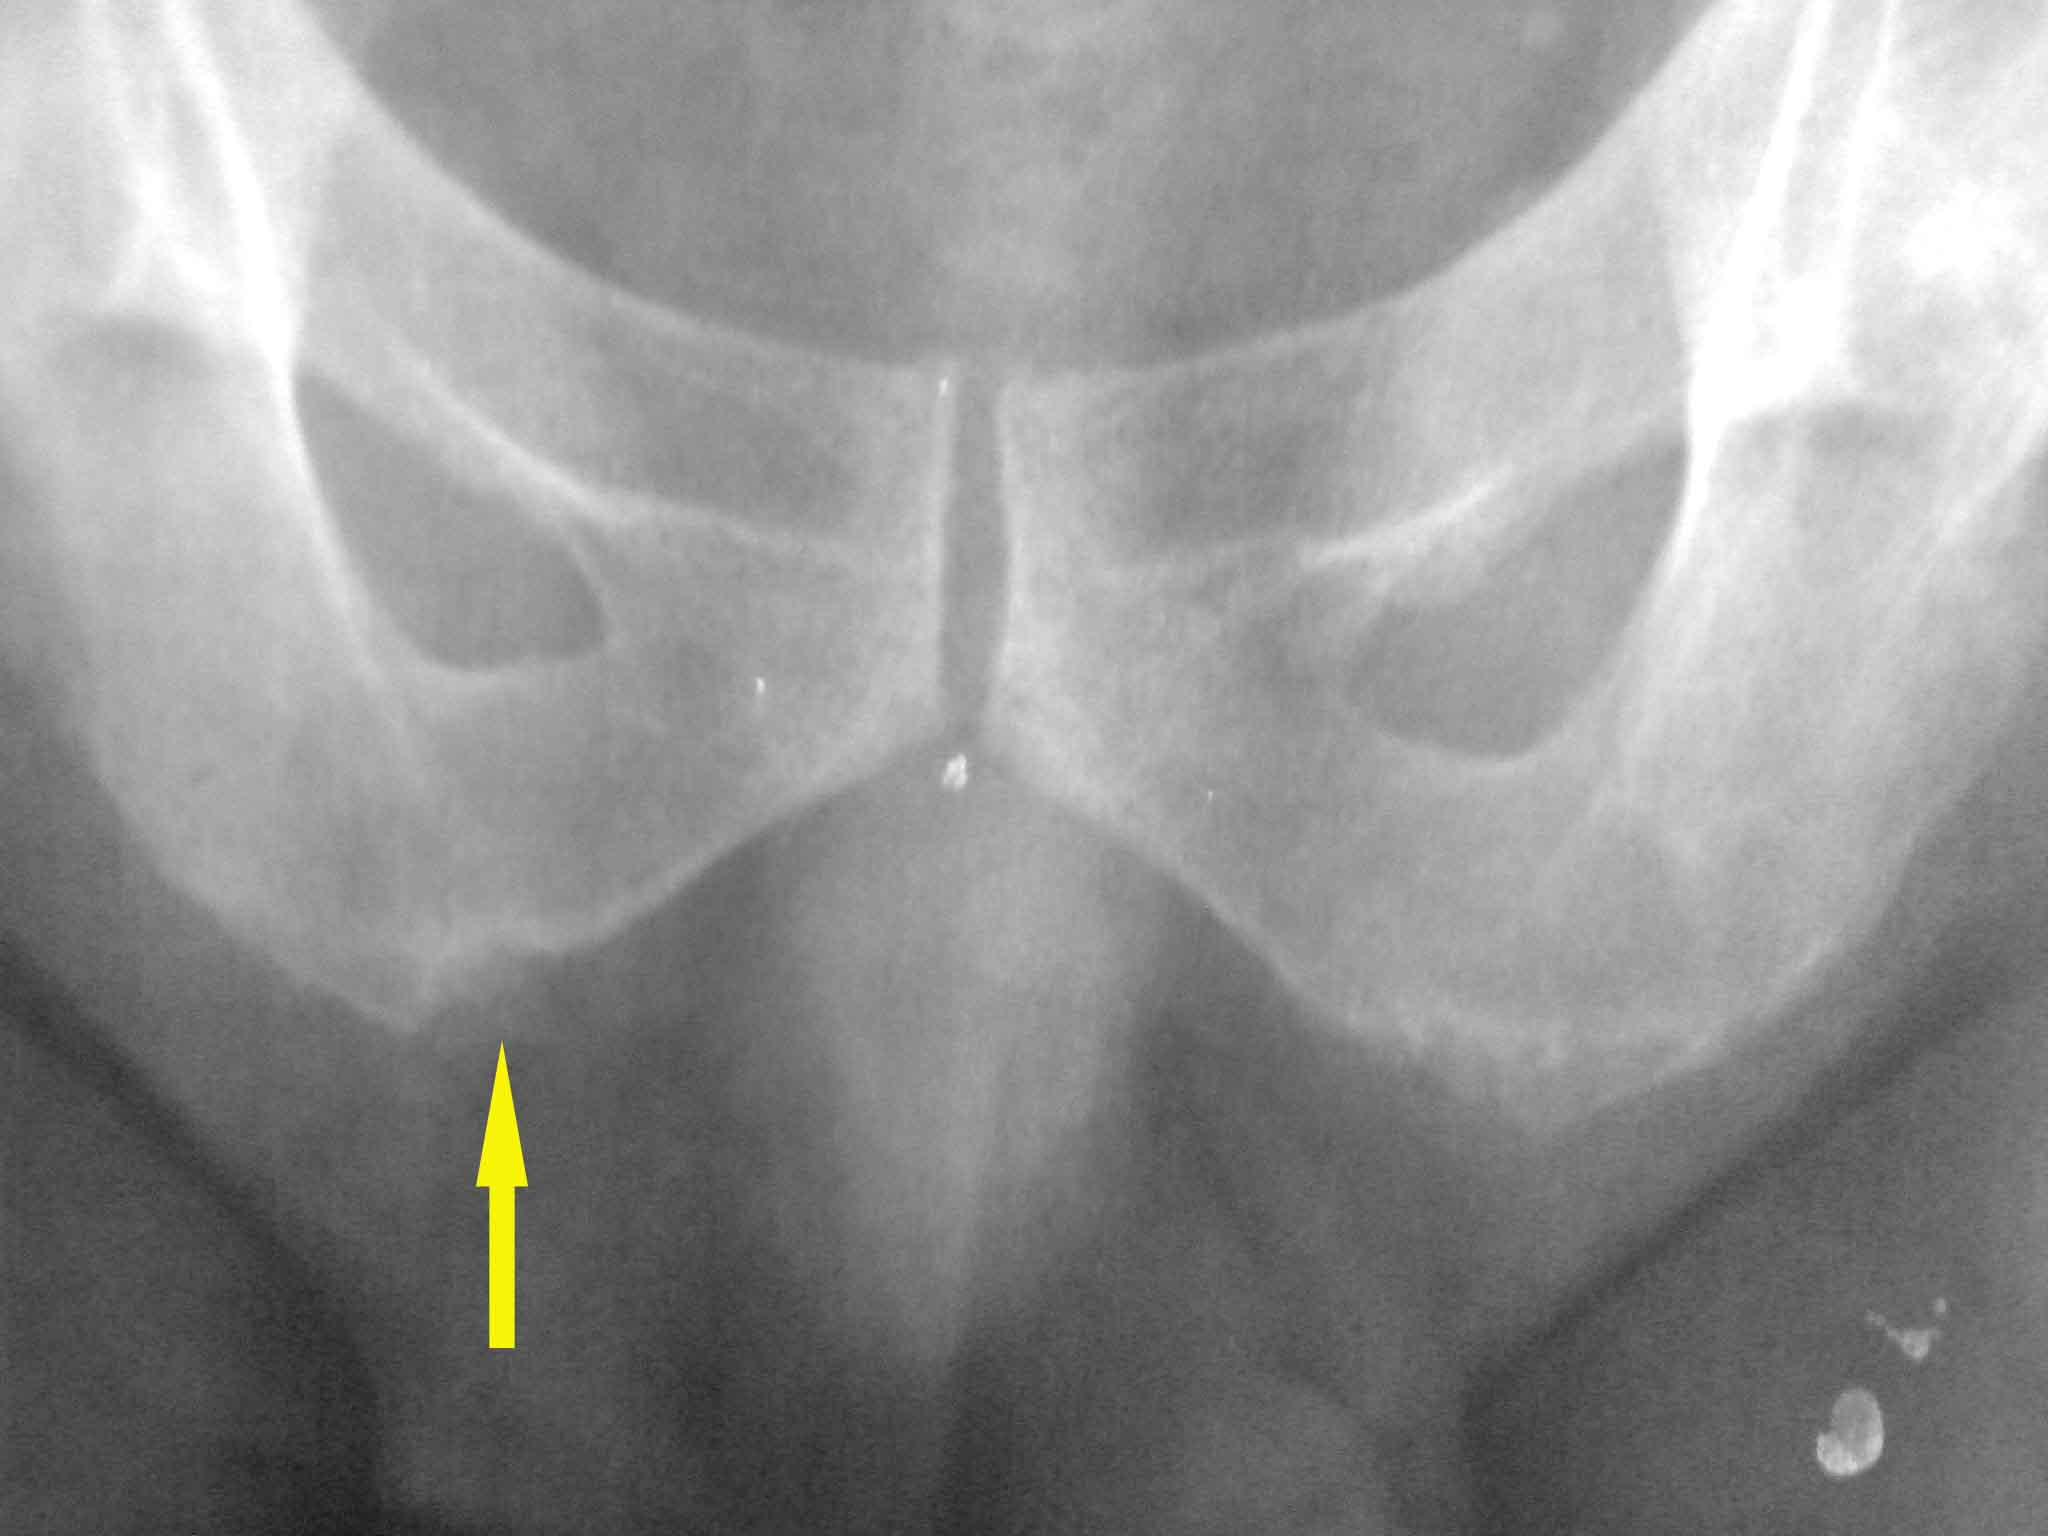

男62岁,右下肢不适,说不出的难受3年,夜间严重,难以入睡,须下地活动或用力捶击下肢才有所缓解,白天无明显疼痛。右坐骨结节有压痛不串射,下肢抬高试验(-)。腰椎ct无异常,骨盆片右坐骨结节与对侧对比似有缺损,是否病变?

如果不放心可以做一下ct.我认为是正常变异.

如果有长期跪坐史,考虑坐骨创伤性附着病。